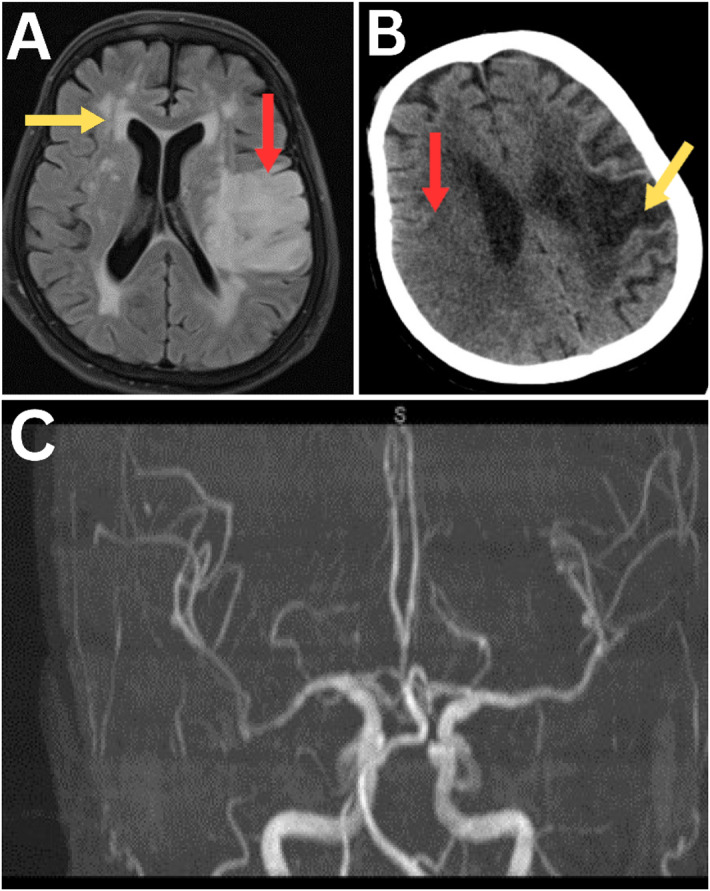

Abstract Image